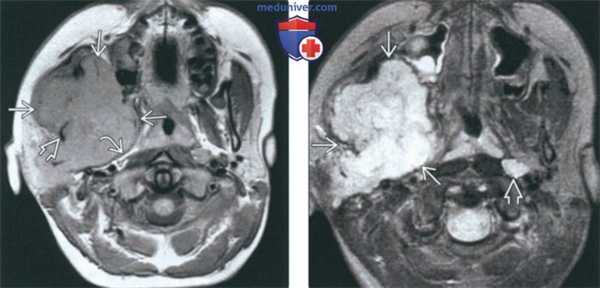

(Слева) При МРТ Т1ВИ в аксиальной проекции определяется объемное образование с сигналом промежуточной интенсивности, которое деформирует жевательное пространство и смещает кпереди заднюю стенку левой верхнечелюстной пазухи. Во всех последовательностях видны небольшие участки низкой интенсивности сигнала, которые представляют собой кальцификаты.

(Справа) МРТ Т2ВИ в аксиальной проекции, этот же пациент. Новообразование имеет гиперинтенсивный сигнал, характерный для опухолей хрящевой ткани. (Слева) МРТ Т1ВИ с КУ, аксиальная проекция, этот же пациент. Образование имеет неоднородную структуру и интенсивно накапливает гадолиний.

(Справа) КТ с КУ в аксиальной проекции, костное окно, этот же пациент. Определяется крупное новообразование, в толще которого «рассеяны» кальцификаты, образующие кольца и арки. Это типичные хрящевые кальцификаты. Наличие кальцификатов обычно говорит о низкой степени злокачественности опухоли.

(Слева) На аксиальной МРТ (Т1 ВИ C+) в жевательном пространстве визуализируется лейомиосаркома высокой степени злокачественности, неравномерно накапливающая контраст и поражающая нижнюю челюсть. Большинство типов сарком жевательного пространства сложно дифференцировать в отсутствие костного или хондроидного матрикса.

(Справа) На корональной МРТ (Т1 ВИ С+ FS) у этого же пациента визуализируется контрастирующаяся опухоль с интракраниальным распространением через овальное отверстие а и поражением кавернозного синуса.

(Слева) На аксиальной МРТ (Т1ВИ) в жевательном пространстве визуализируется саркома Юинга в виде огромного объемного образования с гиперинтенсивным относительно мышц сигналом. Ветвь нижней челюсти разрушена, на этом изображении виден лишь ее мелкий фрагмент. Полоска окологлоточного жира смещена кнутри.

(Справа) На аксиальной МРТ (Т2ВИ FS) у этого же пациента определяется неоднородный сигнал крайне высокой интенсивности в опухоли. Хорошо различимый заглоточный лимфоузел слева является случайной находкой.